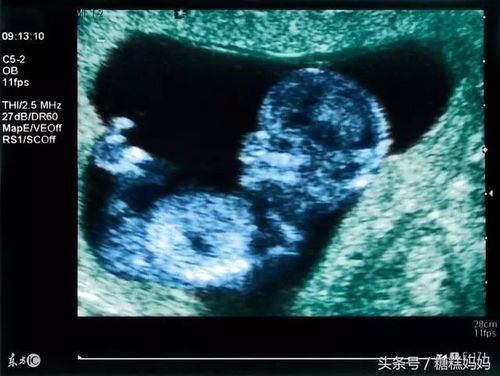

四维彩超男孩清晰图

生过男宝的四维b超图